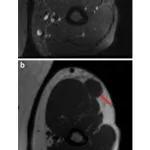

15時過ぎに外来に降りて, 腰痛の急患と指骨の内軟骨腫の患者さんに造影MRIの結果説明.